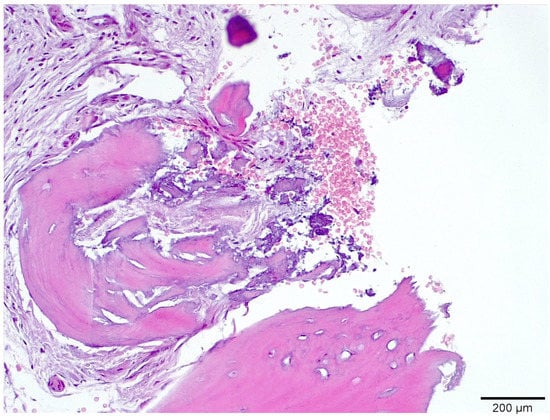

3.1. Histological Analysis Showed Signs of New Bone Formation at 60 Days

3.2. Histologic Data Obtained after Samples Analysis at 24 Months of Evaluation